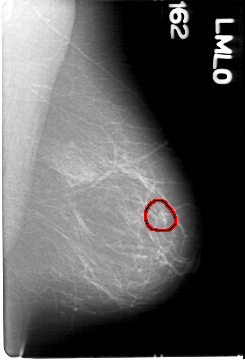

D_4039_1.RIGHT_MLO

LEFT_MLO LINES 5386 PIXELS_PER_LINE 3661 BITS_PER_PIXEL 12 RESOLUTION 43.5 OVERLAY

FILE: D_4039_1.LEFT_MLO.OVERLAY

TOTAL_ABNORMALITIES 1

ABNORMALITY 1

LESION_TYPE MASS SHAPE OVAL MARGINS OBSCURED

ASSESSMENT 0

SUBTLETY 5

PATHOLOGY BENIGN

TOTAL_OUTLINES 1

BOUNDARY